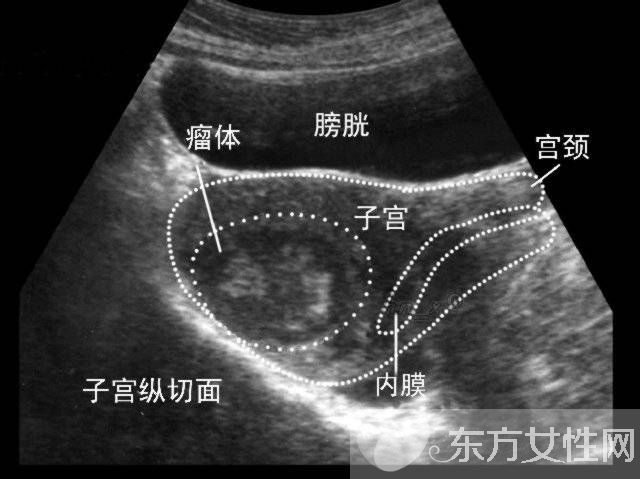

子宮肌瘤是女性子宮內(nèi)多見的非惡性腫瘤,根據(jù)其在宮體內(nèi)肌肉分布位置的不同,可分為肌壁間肌瘤、漿膜下肌瘤和黏膜下肌瘤,不過,肌瘤也可以同時在多種位置生長。